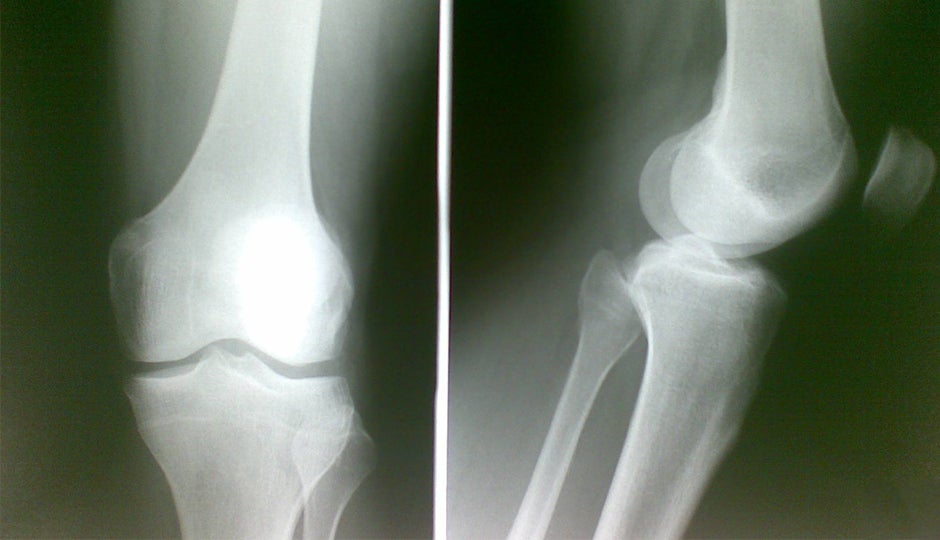

Climbing Knee Injury Prevention . To prevent reinjury of the knee, the authors recommend that rope climbing should be preferred to bouldering to “avoid falls and direct impact on the knee”. If you boulder one day, lead climb the next day, do top rope laps on moderate routes the third day, and be sure to take rest days. 1 in this article, we’ll talk about how to identify, prevent,. The best way to prevent trigger finger syndrome is to mix up your climbing style and training routine. Climbers stress the knees, especially when heel hooking, kneebarring, and highstepping, or taking bouldering falls — in. They also recommend that when bouldering, “down climbing” (a cautious decent) or a “top out” (an alternative easy decent), should take preference to jumping down. One of the more common parts of the knee injured while climbing is the medial meniscus. If you have any concerns or current injuries it is best to consult a physiotherapist. Understanding the various types of climbing knee injuries and their causes enables climbers to prioritize injury prevention.